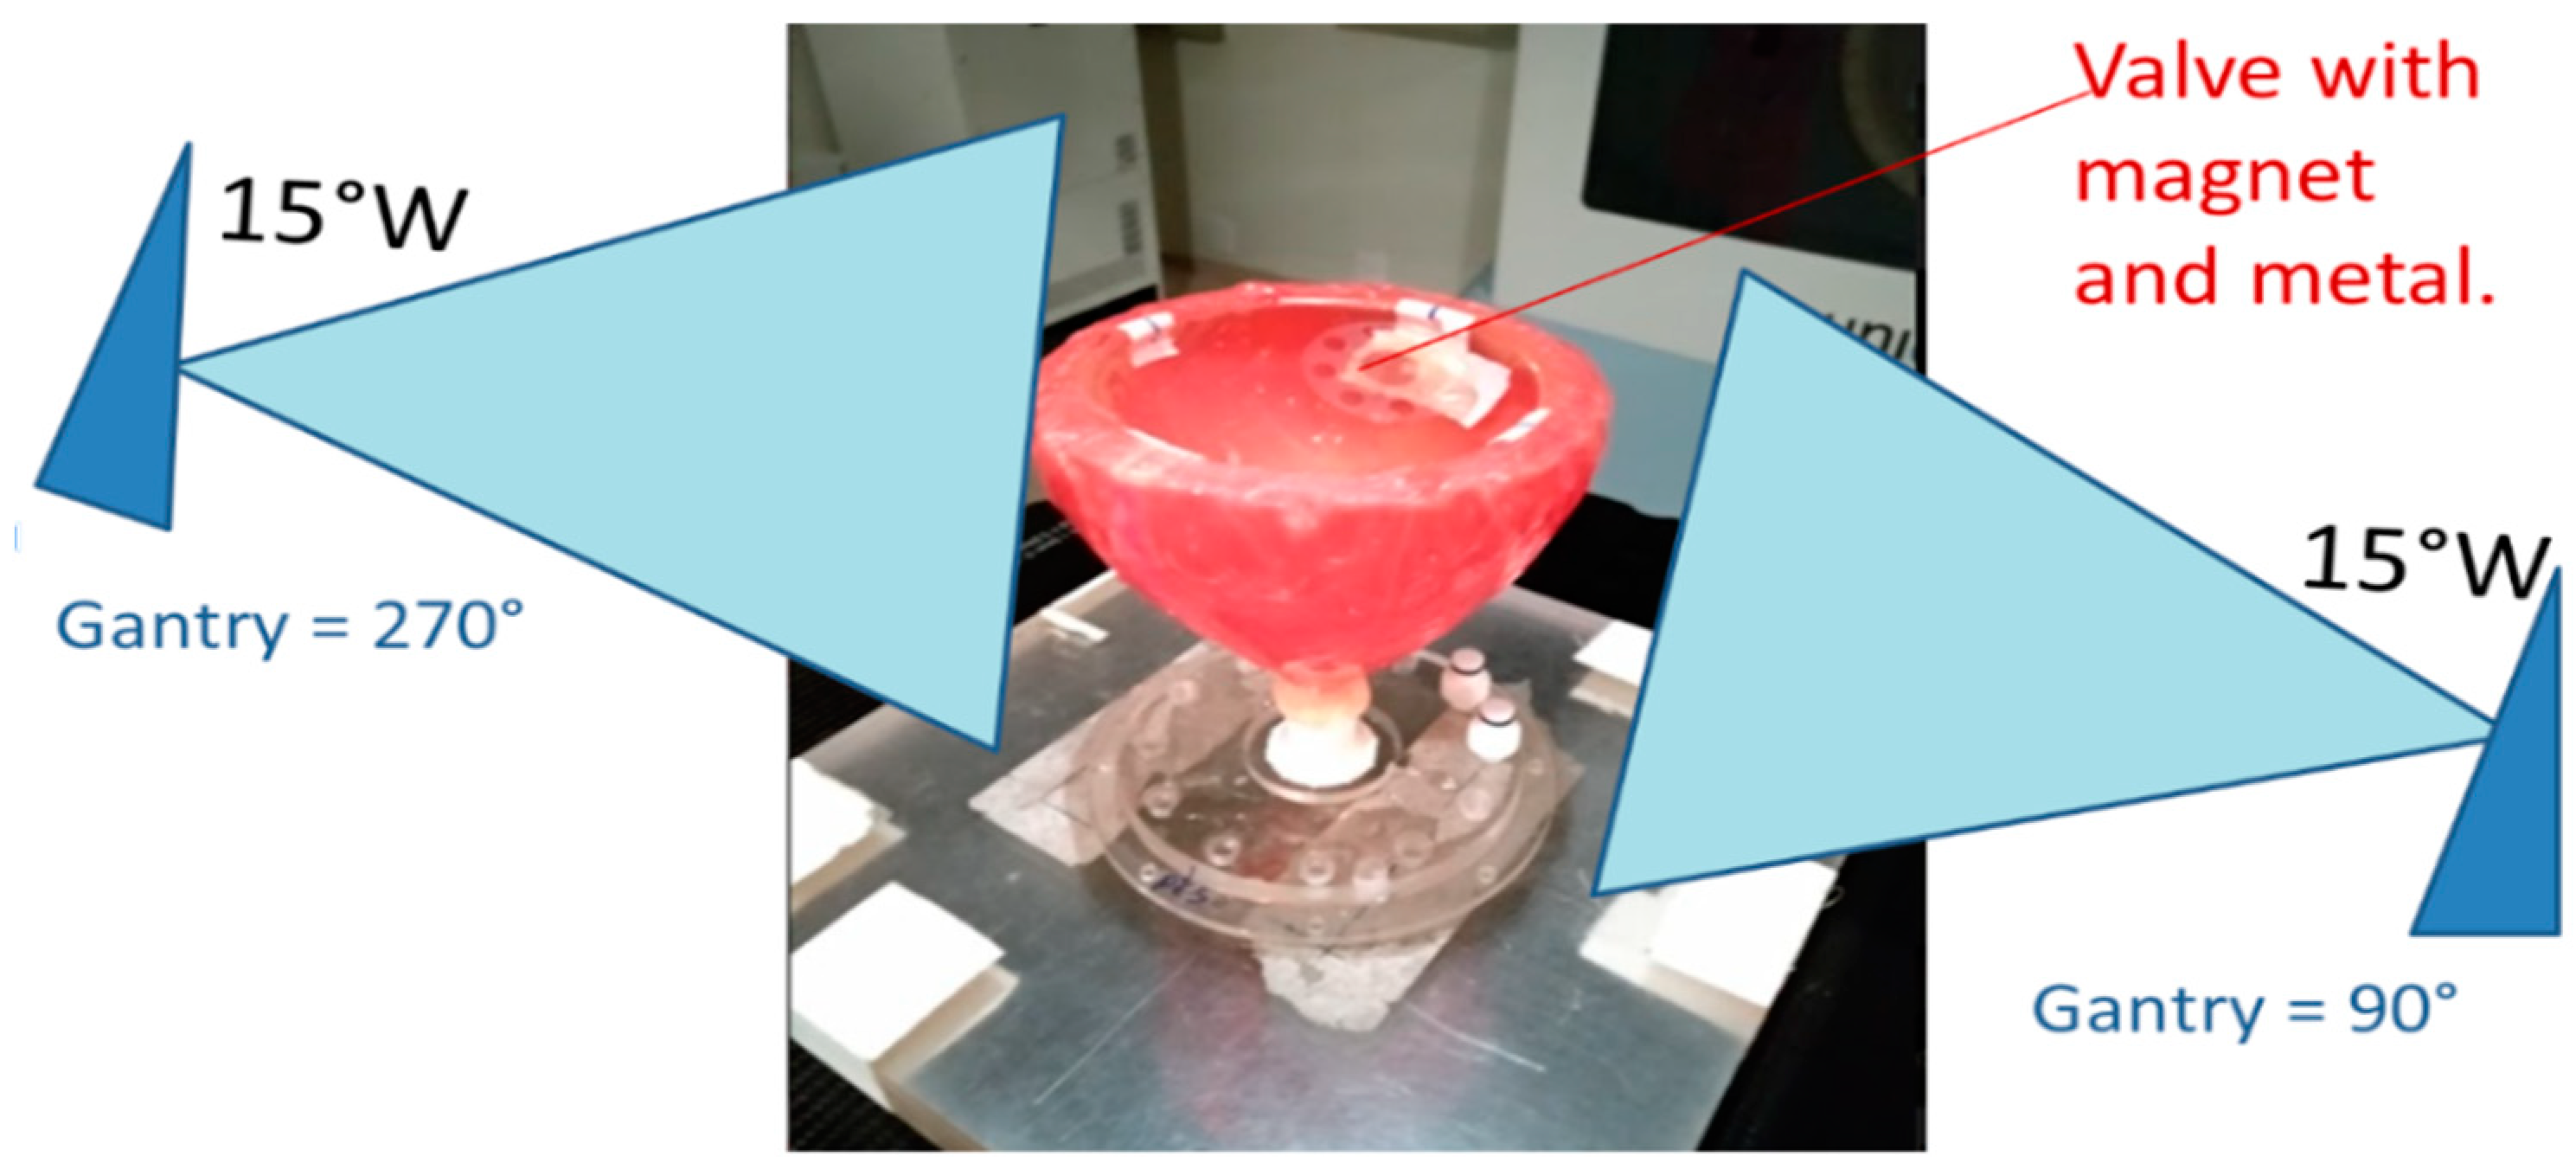

2. Results and Discussion

4. Materials and Methods